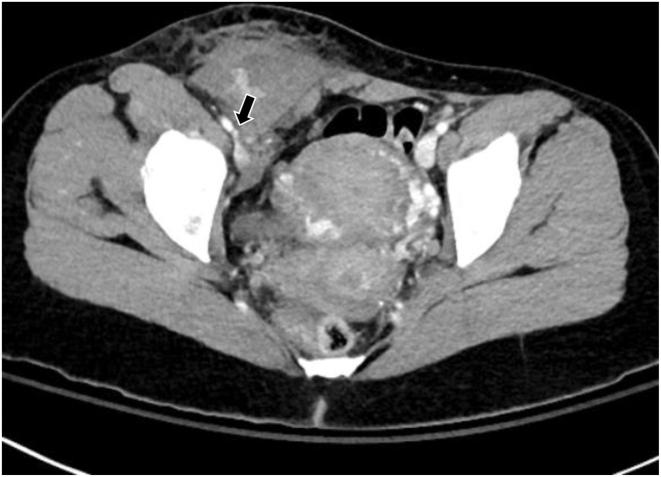

Right anterolateral abdominal wall hematoma following a concealed left anterolateral accessory pathway ablation.